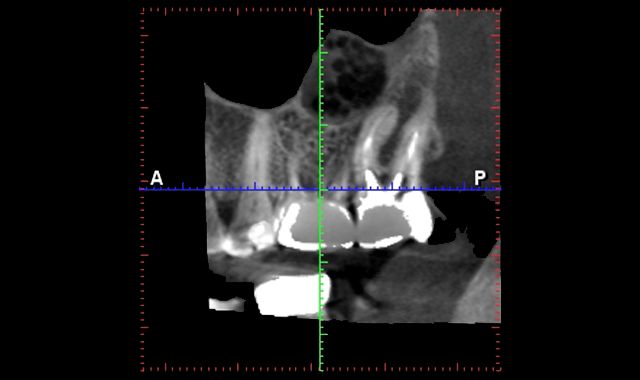

Patients are blown away when they see a three-dimensional image of their jaw. When I can show patients where I can place an implant in their jaw using their own anatomy and a chairside model, patients can visualize and comprehend the procedure more clearly. I would encourage the use of videos that all the major dental implant companies produce. Check with their marketing department and incorporate a video into your website. While the patient is in the chair, you or your team can pull it up on your website for the patient to view. This serves two purposes. First, patients can visualize it more clearly. Second, when they go home to their significant other, they can pull up your website and explain the procedure to them.

Having an intraoral scanner and a cone beam is the perfect marriage. Both are completely independent of each other. The scanner focuses on teeth and tissue and the cone beam addresses the bony architecture. When the STL files are joined in the lab, there is complete harmony. Like a great marriage, they make each other better. From my understanding and speaking with different vendors, one can take a DICOM file obtained from the CBCT, convert it, make a virtual model, 3D printed model and fabricate a crown. So, in theory, you could prep a tooth and have an edentulous area. Plan the implant and make the crown or partial all at the same time. And then there are times we just need to take an intraoral scan and make a crown inlay or onlay.